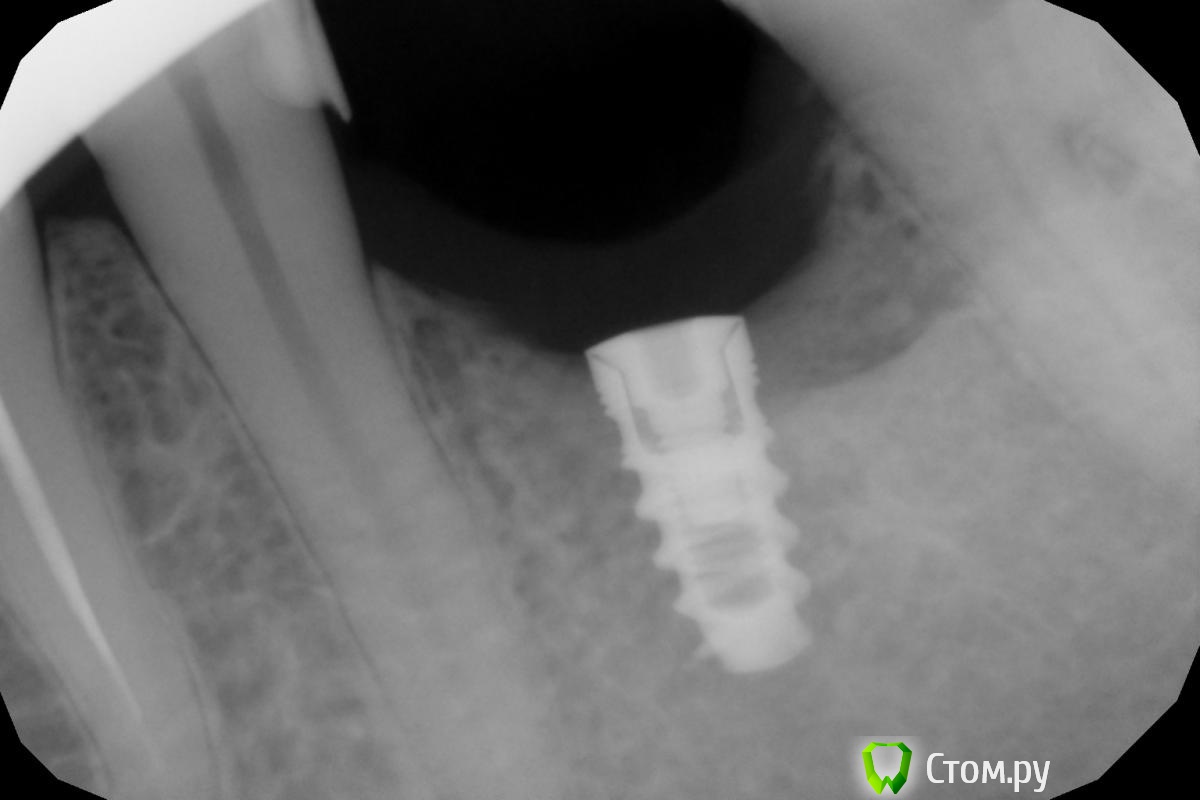

Шамонов Дмитрий Опубликовано 13 января, 2014 Поделиться Опубликовано 13 января, 2014 Уважаемые коллеги!!!Подскажите, что за система импланта на прикрепленном файле.Заранее благодарю!!! Ссылка на комментарий

Шамонов Дмитрий Опубликовано 13 января, 2014 Автор Поделиться Опубликовано 13 января, 2014 Я просмотрел три системы Alfa, Mis, Adin.они все немного отличаются. Ссылка на комментарий

wladdX Опубликовано 14 января, 2014 Поделиться Опубликовано 14 января, 2014 На MIS7even похоже Ссылка на комментарий

m.d.n Опубликовано 14 января, 2014 Поделиться Опубликовано 14 января, 2014 alfa dent я такие недавно удалял Ссылка на комментарий

Rash163 Опубликовано 17 января, 2014 Поделиться Опубликовано 17 января, 2014 Это ни мис7 точно, какой то другой Израильтянин) фотка мис7) мелкие витки другие, ну и крупные тоже отличаются. Ссылка на комментарий